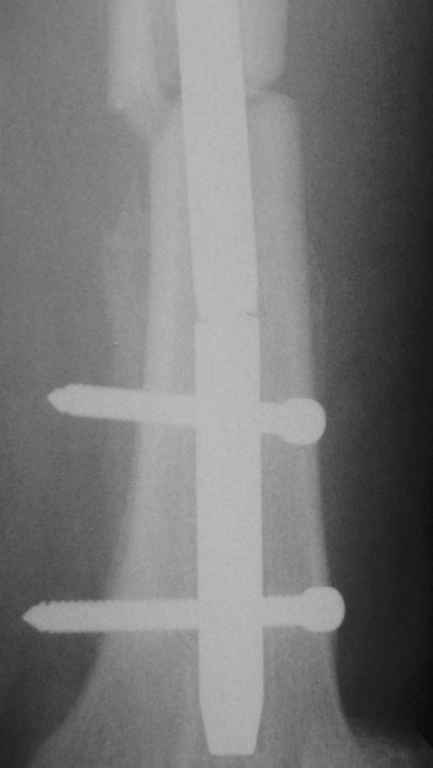

Пациентка 40 лет, 6 мес назад был произведен интрамедуллярный синтез бедра канюлированным гвоздем без рассверливания. Обратилась в связи с появлением болей в бедре.

На Р-контроле – перелом гвоздя как следствие отсутствия динамизации конструкции (пациентка не обращалась в отделение). Планируем интрамедуллярный реостеосинтез с рассверливанием, однако возник вопрос о способе удаления дистального фрагмента гвоздя: с одной стороны – не хотелось бы беспокоить область перелома (разъединять отломки), с другой – лезть через колено-тоже не очень. Есть ли какие другие методы (удаления м/к) в данном случае?